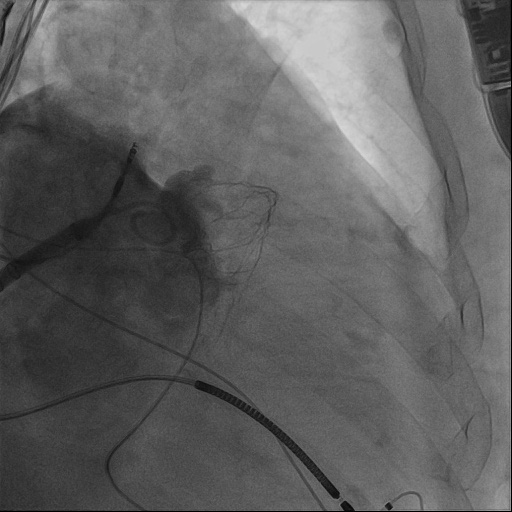

心血管内科团队与超声诊断科、麻醉科进行了术前会诊,对钟婆婆病例进行研讨分析,制定了周密手术方案及并发症应急预案。术中唐波副主任医师与沈松林主治医师通力合作,经右侧股静脉,在食道超声引导下穿刺房间隔,将长鞘顺利进入患者左心耳,利用猪尾导管进行造影,同时进行测量,选择合适的封堵器封堵左心耳。术中,超声诊断科为钟婆婆实时进行经胸、经食道超声心动图检查,以实时精密的测量为手术医师提供有效可靠地帮助;麻醉团队为钟婆婆诱导麻醉、气管插管、全麻和机械通气及全程监测,各学科通力配合,顺利完成手术。

图3、患者左心耳封堵器释放后,造影评估左心耳封堵效果,患者左心耳封堵成功。